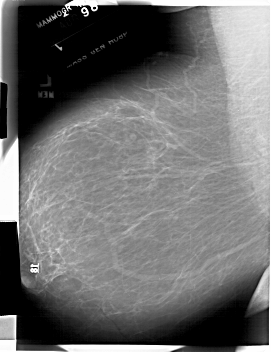

A_1843_1.LEFT_MLO

LEFT_MLO LINES 6676 PIXELS_PER_LINE 5146 BITS_PER_PIXEL 12 RESOLUTION 43.5 NON_OVERLAY